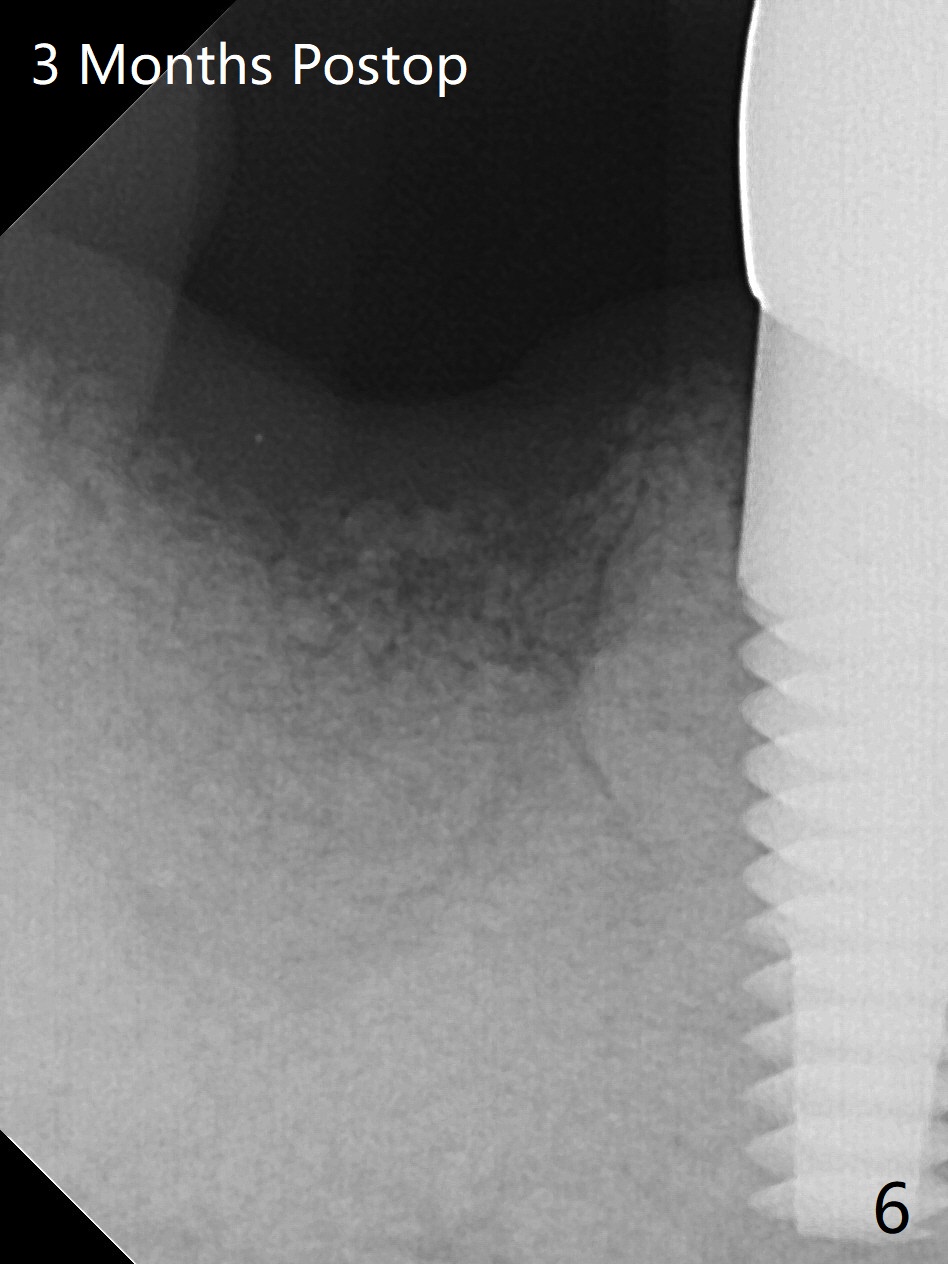

A 88-year-old man returns with pain and swelling (Fig.1), one year after diagnosis of #31 mesial root fracture. After discussion, the tooth is extracted with socket preservation (Vanilla graft mixed with Osteogen, covered with Osteogen plug and Collagen plug, Fig.2,3). The buccal crest is much lower than the lingual one. The socket opening reduces with resolution of 4-0 Chromic gut suture 1 week postop (Fig.4). The wound is wider with foul odor 2 weeks postop (data not shown). The socket and ridge shrink with loss of the bone graft 3 weeks postop (Fig.5). The bone volume reduces with buccal plate collapse 3 months postop (Fig.6,7). Immediate implant and provisional should be able to help restore the lost buccal plate. The buccal plate remains concave 5 months postop (Fig.8,9). The coronal section shows that there is space (Fig.10 *) buccal to the graft (G). A 2.0 mm pilot drill is used to create an initial osteotomy through the graft zone and in the beginning of the native bone (Fig.11,12). Use bone expanders (Fig.13 E) to push (arrowheads) and condense the graft bone and close the buccal gap. The apical portion of the osteotomy requires regular drills (Fig.14 D).